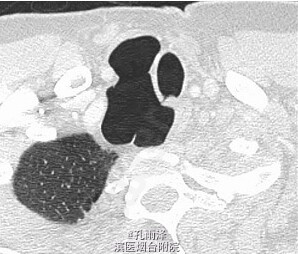

病史:患儿女,1d,因“气促、喉鸣1d”入新生儿重症监护室。患儿足月剖宫产分娩,Apgar评分:1min6分,5min9分,羊水正常,出生体质量4000g。生后口周紫绀、气促、喉鸣。

查体:足月新生儿貌,反应稍差,躯干、四肢可见散在针尖大小出血点,三凹征(+),双肺呼吸音粗糙,对称,可闻及吸气相喘鸣音及粗湿啰音。 实验室检查:血气分析:pH7.319,氧分压(P02)90mm.Hg,二氧化碳分压46.5mmHg,BE-2mmo]/L。血常规:白细胞(WBC)20.57×109/L,N 83.80%。尿钙试验(+)。Pr系列:血浆凝血酶原时间15.2s,活化部分凝血活酶时间53.08,血浆凝血酶时间测定20.7s。

诊断:(1)气管憩室;(2)新生儿肺炎;(3)巨大儿。 处理:予心电监护,维持水、电解质、酸碱平衡,供给足够的热卡,抗感染、制酸止血、营养心肌等治疗。住院2d病情控制出院。嘱定期复诊。